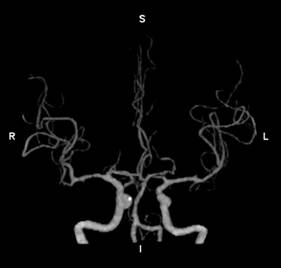

2、脑卒中一站式完成多期扫描

Apex CT通过DLIR技术,突破以往CT需要多次打药、多次扫描的弊端,实现一次对比剂注射下得到CTA、CTV、灌注等临床所需图像,极大缩短抢救患者检查时间。